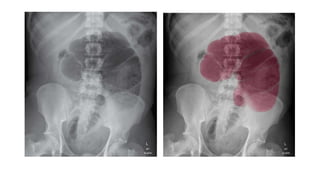

SOLID ORGAN ENLARGEMENT

Either by increase in the overall size of one of the solid organs or by a large

RADIOLOGICAL SIGNS :

•Large soft tissue density (light grey)mass

•Loops of bowel often displaced by the mass

•Location gives a clue

RUQ – liver , right kidney

LUQ – spleen ,left kidney , fluid filled stomach

Lower abdomen – ovaries,uterus , distended urinary bladder.